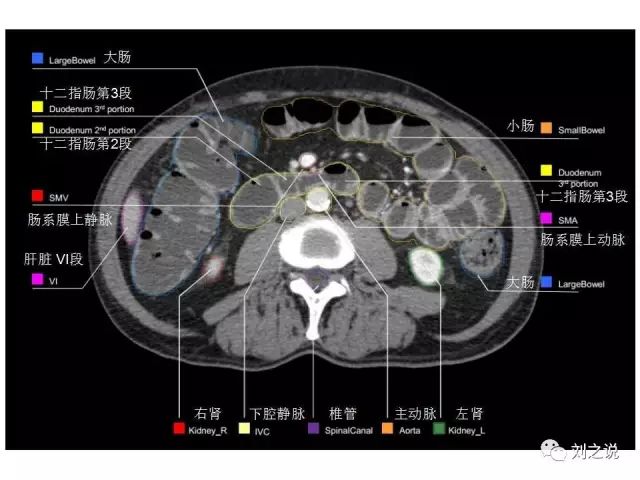

参考RTOG共识和3D-body解剖。

来源:刘之说